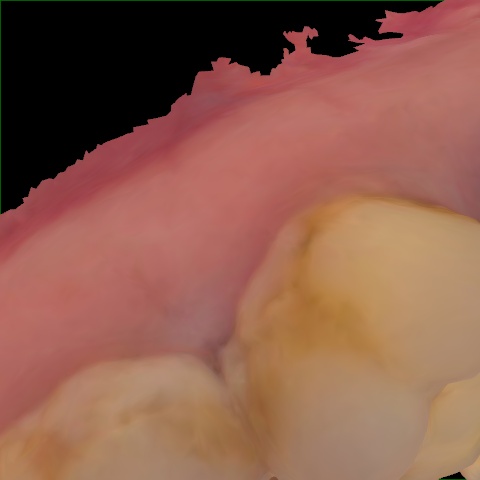

Annotated as "Good"